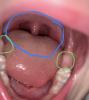

Тогда что это? Уже долгое время наблюдаю - все белеет и увеличивается в размерах.

Сейчас опять стал плохо есть и просит пюре. Из-за красного горла? Или это новые зубы + красное горло?

Белое это новые зубы. У дочки их еще нет, лезут еще, а у кого то ещё к трем годам вылезли